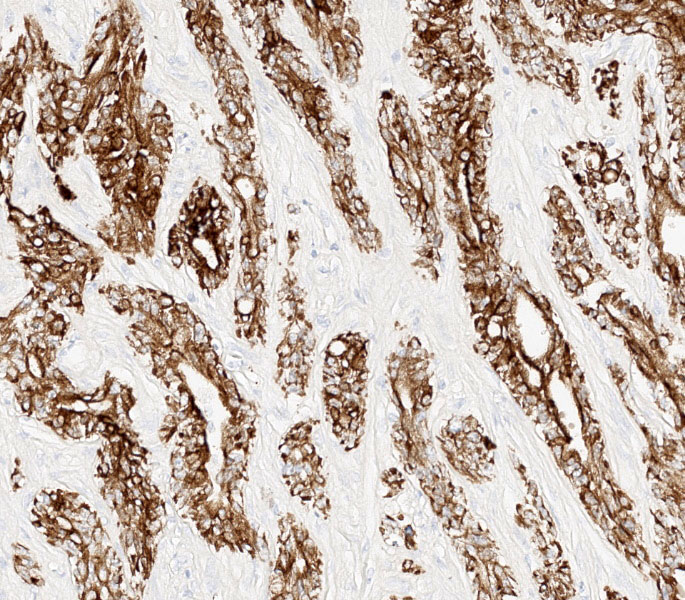

Differential diagnoses for this urinary bladder mass included urothelial cell carcinoma, prostatic carcinoma, and renal carcinoma, with the latter two included largely to ensure that metastatic or locally invasive disease was not being overlooked. The histologic architecture of an infiltrative epithelial neoplasm seemingly arising from the bladder wall favored a urothelial origin, but immunohistochemistry provided an additional layer of information. The neoplastic cells were diffusely immunoreactive for CK7, a cytokeratin expressed in most primary urinary bladder carcinomas.4 They were negative for GATA3, a transcription factor involved in urothelial differentiation, which may suggest prostatic carcinoma instead.5 However, Dr. Alves noted that GATA3 is most reliable in well-differentiated urothelial carcinomas, and its absence here is also consistent with less well-differentiated UCCs, as in this case.5 The tumor was also negative for PAX8, a marker of renal tubular epithelium, which helped exclude renal carcinoma.2 Uroplakin, a highly specific marker for urothelial cell carcinoma, unfortunately did not work in this case.7 Participants also discussed the glandular differentiation present within the tumor, which can be seen in both urothelial cell and prostatic carcinomas. In humans, glandular differentiation in urothelial carcinoma is associated with invasion and poorer differentiation.8 While extrapolating across species is something to be avoided, the same pattern was evident here.